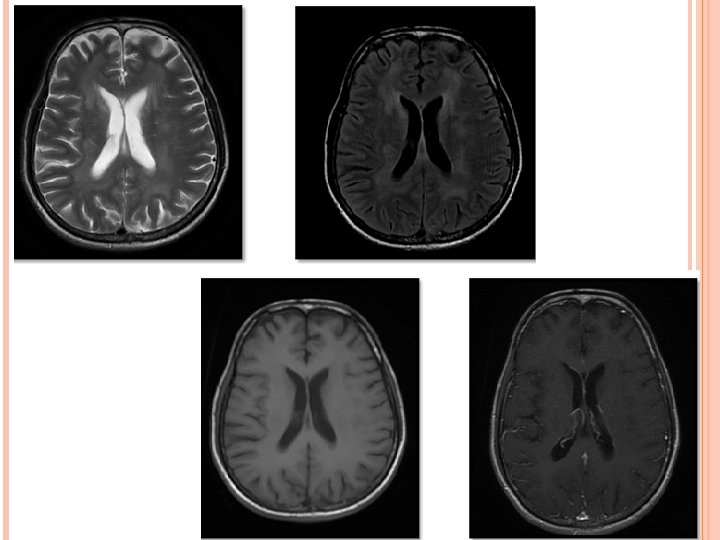

HIV ENCEPHALITIS NECT- Normal or atrophy +/- WM hypodensity. MR • • • v Volume loss with prominent sulci and ventricle. T 2/FLAIR hazy symmetric WM hyperintensity, spare the subcortical U fibers. No mass effect. Usually no enhancement and no restricted diffusion. T 1 images reveal no hypointensity. Reduced grey matter volume in superior and medial frontal gyri – possible early imaging marker. D/D- PML, CMV enchephalitis, ventriculitis; toxoplasmosis; Herpes and HHV-6 encephalitis.